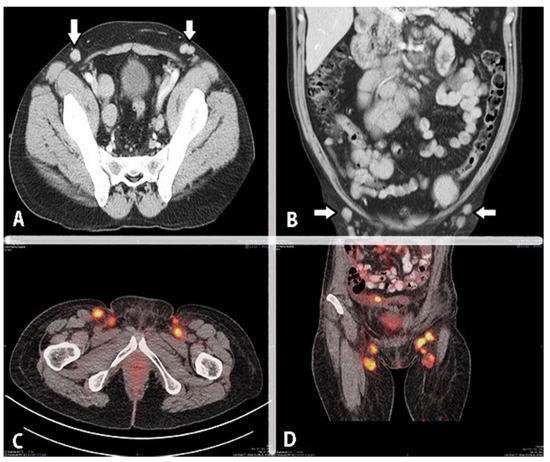

8. Cardiophrenic Lymph Nodes

9. Inguinal Lymph Nodes Anatomy